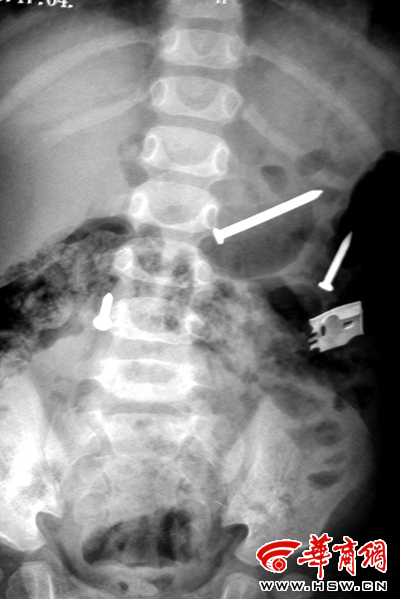

排出鐵釘之后復(fù)檢拍片又顯示肚內(nèi)有鐵釘(劉立春攝)

來自榆林市米脂縣的這名一歲半女孩,在最近一個多月內(nèi),從體內(nèi)不斷排出鐵釘,共達(dá)20多枚。更為奇怪的是,在醫(yī)院拍片顯示體內(nèi)已沒有鐵釘時,過幾天鐵釘還會出現(xiàn)。

榆林市兒童醫(yī)院兒外科醫(yī)生申志軍告訴記者,醫(yī)院本來準(zhǔn)備對女孩再觀察幾日,以確保孩子身體健康,但是19日上午,女孩的父母卻突然要求辦理出院手續(xù),并且態(tài)度非常堅決。無奈之下,醫(yī)院給孩子做了一次X光片檢查!白詈笠粡圶光片顯示,女孩體內(nèi)沒有異物。醫(yī)院經(jīng)過研究,同意出院了。”申志軍說。